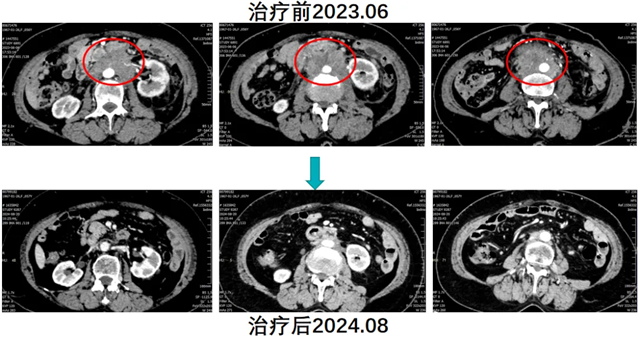

经肿瘤四科(头颈盆腔食管肿瘤科)团队充分讨论,建议患者行腹主动脉旁淋巴结空间分割放疗联合免疫治疗(卡瑞利珠单抗)及生物治疗(人粒细胞巨噬细胞刺激因子)。与患者及家属沟通病情并经同意后,实施了上述治疗方案。放疗后患者返院高兴的讲述道腹部疼痛已经没有了,复查CT显示腹腔淋巴结明显缩小,治疗效果显著,续继免疫维持治疗。患者肿瘤持续缩小、生活质量明显提高,今年8月复查显示肿瘤基本消失。

患者就诊时已属于晚期子宫内膜癌,且对免疫联合化疗耐药,可选择治疗手段非常有限。患者如果不尝试“鸡尾酒”(空间分割放疗联合免疫及生物治疗)式疗法,预计生存时间不超过半年。通过“鸡尾酒”疗法成功逆转了免疫耐药,极大地延长了患者的生存时间,明显提升了患者的生存质量。